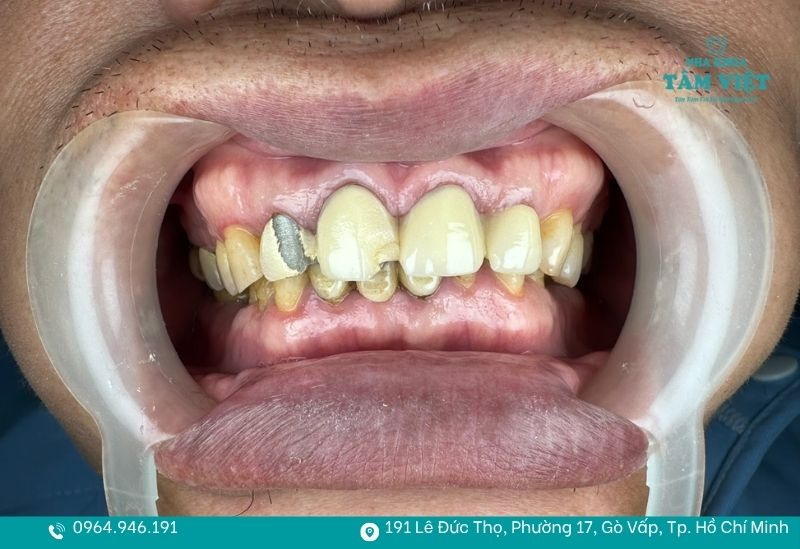

Tuổi thọ của răng sứ chịu ảnh hưởng lớn từ chất liệu và trình độ chuyên môn của bác sĩ. Những loại răng sứ cao cấp có độ bền cao và khả năng giữ màu tốt theo thời gian. Ngược lại, răng sứ kim loại dễ xuống cấp và có thể xuất hiện viền đen ở nướu sau một thời gian sử dụng. Bên cạnh đó, kỹ thuật mài răng và lắp mão sứ chuẩn xác cũng góp phần quan trọng giúp tăng độ bền.

- Răng sứ đổi màu, ố vàng hoặc xuất hiện viền đen mất thẩm mỹ.